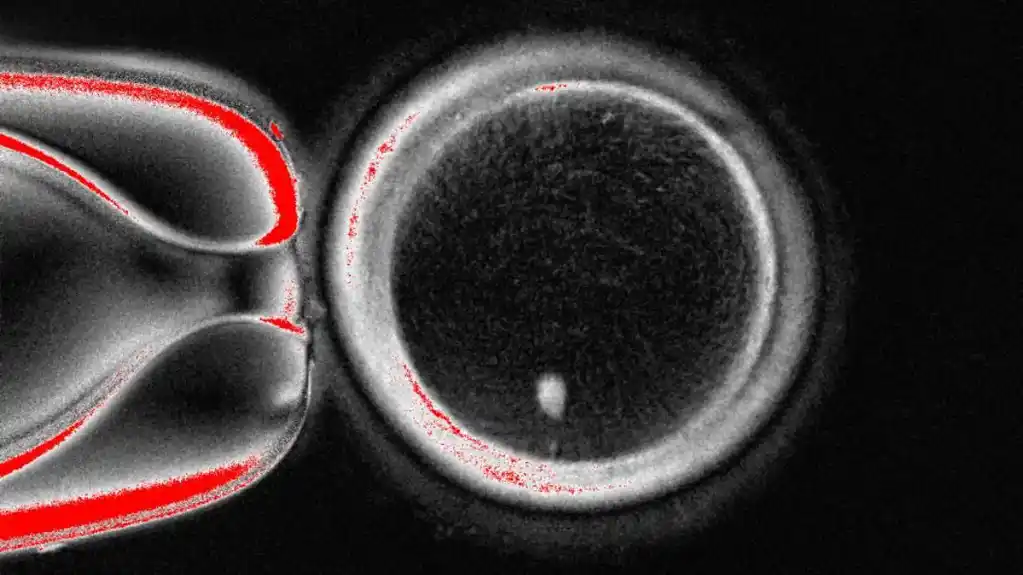

Prema tehnici istraživačkog tima sa Oregonskog univerziteta za zdravlje i nauku, izvadi se jezgro u kojem je kopija čitavog genetskog koda potrebnog za izgradnju tela iz ćelije kože.

On se potom smesti u jajnu ćeliju davaoca kojoj su izbrisana njena genetska uputstva.

Međutim, jajna ćelija nije spremna da bude oplođena spermom jer već sadrži pun komplet hromozoma.

Vi nasleđujete 23 ova DNK paketa od svakog roditelja da biste ih imali ukupno 46, koje jajna ćelija već poseduje.

Sledeći stadijum je ubediti jajnu ćeliju da odbaci polovinu vlastitih hromozoma u procesu koji su istraživači nazvali „ mitomejoza “ (reč je spoj mitoze i mejoze, dva načina ćelijske deobe).

Studija, objavljena u naučnom časopisu Nejčer komjunikejšns , prikazala je da su napravljene 82 funkcionalne jajne ćelije.

Bile su oplođene spermom, a neke su stigle čak do ranih stadijuma razvoja embriona.

Nijedan nije razvijen posle šestodnevnog stadijuma.

Ova tehnika je daleko od usavršene, jer jajna ćelija bira nasumično koje hromozome će odbaciti.

Mora da završi sa po jednim od svakog od 23 tipa da bi se sprečile bolesti, ali na kraju završi sa po dva od jednog i nijednim od nekog drugog.

Postoji loša stopa uspeha (oko devet odsto), a hromozomi promašuju važan proces kad preraspoređuju vlastiti DNK, koji se zove „rekombinacija“.